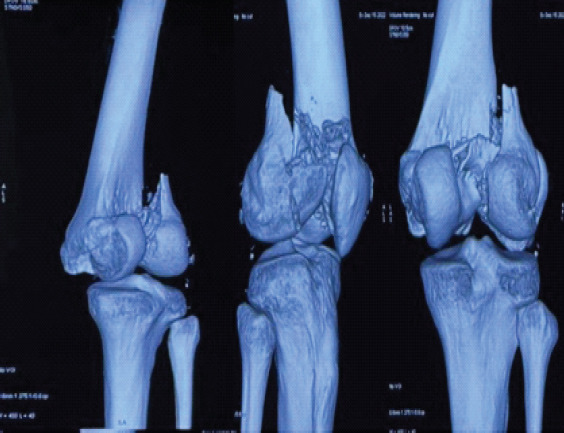

Case report: We present the case of a 25-year-old male who sustained an isolated bicondylar Hoffa fracture following a motorcycle accident. Radiographs and computed tomography (CT) imaging confirmed isolated coronal plane fractures of both femoral condyles (AO 33-B3), without metaphyseal comminution or intercondylar extension. The fracture was managed through a single medial parapatellar approach, using 5 cannulated screws and 2 headless Herbert screws. Post-operative rehabilitation involved early mobilization and progressive weight bearing. At 2 years follow-up, the patient demonstrated excellent functional recovery with a full range of motion (0-140°), no extensor lag, and pain-free full weight-bearing.